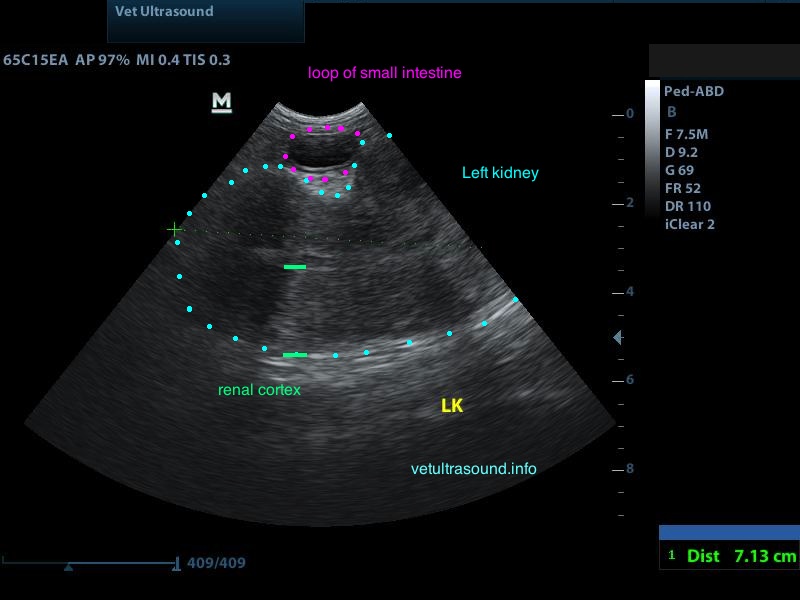

Ευρήματα: Στον υπέρηχο κοιλίας βρέθηκε επώδυνη διόγκωση και των δύο νεφρών με πάχυνση της φλοιώδους ουσίας, η οποία παρουσίαζε έντονη ανομοιογένεια. Οι νεφρικές πύελοι ήταν ήπια διατεταμένοι και στο εσωτερικό τους παρατηρήθηκε αφθονία ιζήματος. Οι ουρητήρες, οι οποίοι ήταν επίσης διατεταμένοι, απεικονίζονταν μέχρι την είσοδό τους στην ουροδόχο κύστη. Αφθονία ιζήματος βρέθηκε στην ουροδόχο κύστη. Η εικόνα αυτή είναι συμβατή με διάμεση νεφρίτιδα και στην συγκεκριμένη περίπτωση με πυοκοκκιωματώδη φλεγμονή των νεφρών, συνεκτιμώντας τα εργαστηριακά ευρήματα, τον έντονο πόνο και τη διάταση των ουρητήρων. Το resistive index ( δείκτης αγγειακής αντίστασης) βρέθηκε αυξημένο (0.77) σε μεσολόβιο αρτηρίδιο του νεφρού. Φυσιολογικά θα έπρεπε να είναι (0.6±0.06). Αυτό δείχνει πως το οίδημα του νεφρικού παρεγχύματος εξαιτίας φλεγμονής ή οποιαδήποτε άλλης διήθησης, νεοπλασματικής ή μη, πιέζει τα αγγεία και αυξάνει την αντίσταση του αίματος προς το νεφρό. Ένα επιπλέον διαγνωστικό βήμα για την διερεύνηση της αιτίας, για την αποτελεσματικότερη θεραπεία και την εγκυρότερη πρόγνωση, είναι η λήψη κυτταρολογικού υλικού από το νεφρικό παρέγχυμα και ούρου από τη νεφρική πύελο για καλλιέργεια, στα οποία ο ιδιοκτήτης δεν θέλησε να προχωρήσει.